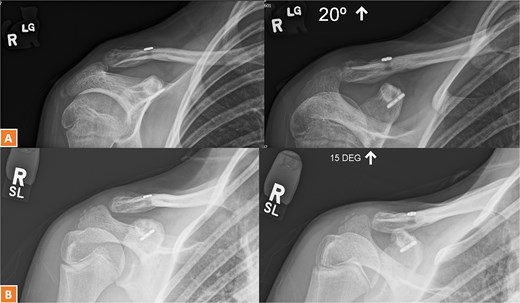

(A–C) Radiographs showing complete healing of the second case and union at 3, 6, and 12 months post-operatively.

A 30-year-old male presented with an unstable lateral clavicle fracture and skin tenting after a rugby injury. Imaging revealed a Neer type IV equivalent fracture (Fig. 3). He underwent open reduction and internal fixation with coracoid exposure and TightRope placement, reinforced with fiber-wire. Postoperative recovery included sling immobilization followed by pendular exercises. Despite delayed radiological union, he achieved full range of motion and strength by three months, with only mild, asymptomatic clavicular prominence. He returned to physically demanding work without restrictions, and final imaging confirmed union (Fig. 4A–C).